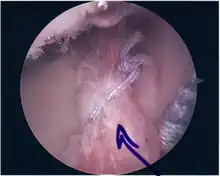

Repair of SLAP tear

- The suture component of the implant is tied through the labrum and knotted such that the labrum is in tight contact with the glenoid surface.